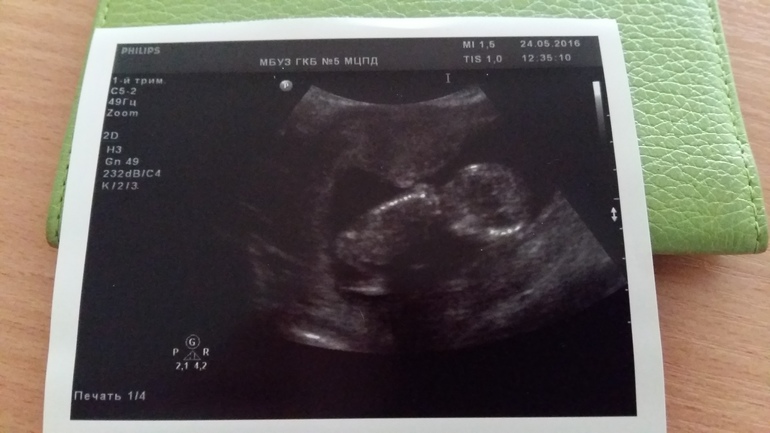

Вот и наш 1 скрининг) 13 неделя,фотки

Узи пройдено! Все хорошо. Малявочка моя активная,не так то просто было уловить. Но все померяли. Ктр 58мм,носик 1.4, сердцебиение 162. сидит по-турецки из-за чего пол не смогли даже предположить) ручки и ножки симметричны. Все что необходимо- визуализируется. Было прикрепление сзади низковато. А сейчас- справа и не низко, как сказала врач) все узи записали и это видео потом показали мне,а муж спустился на минуту и именно когда его хотели позвать. Обидно,но ладно. Сам виноват))) вот и наше первое фото